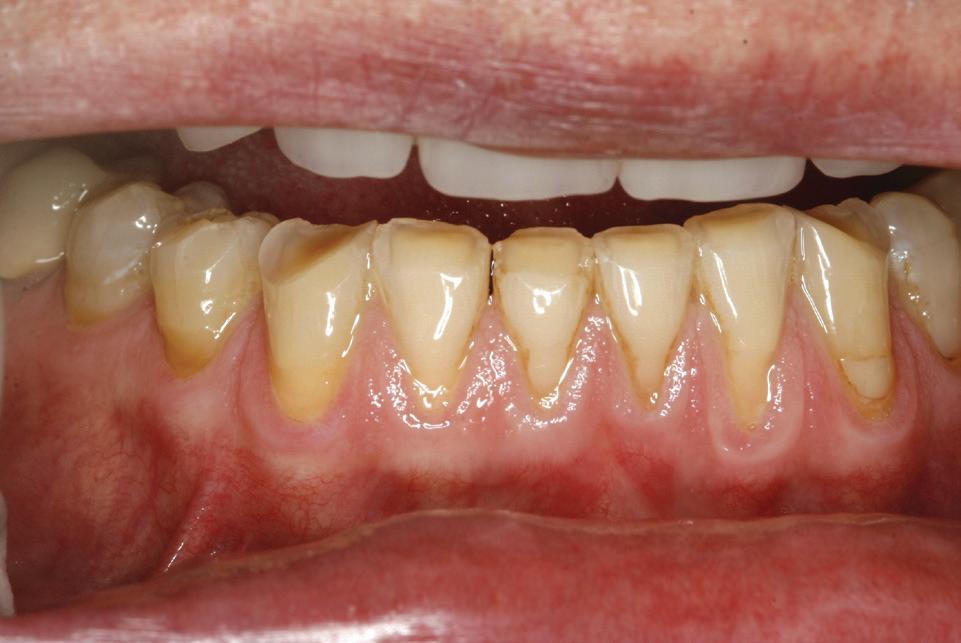

Un pacient caucazian în vârstă de 77 ani s-a prezentat la clinica autorului după cinci ani în care nu a fost la niciun control stomatologic. Examinarea clinică a arătat o pierdere semnificativă de os, parodontită cronică și multiple edentații care au destabilizat ocluzia. Pacientul a raportat sensibilitate la rece la nivelul primului molar drept inferior nr. 46, în special la ingerarea de lichide reci. Radiografia periapicală a confirmat constatările examenului clinic; în

plus, s-a detectat și prezența unei carii radiculare la nivelul rădăcinii distale a aceluiași molar, cu răspuns pozitiv la testul de sensibilitate (fig. 1-2).

1. Situația clinică inițială.